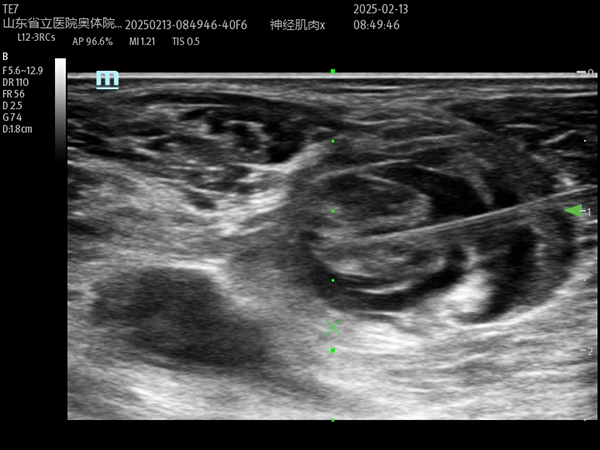

超声引导下右侧下肢腘窝坐骨神经阻滞

麻醉手术科副主任医师李旺在副主任医师马金本和医师刘聪协助下,在超声引导下精准完成了右腿的髂筋膜阻滞和腘窝坐骨神经阻滞,经过测试阻滞后镇痛效果良好。考虑到患者一般状态较差若同时进行两侧下肢神经阻滞,有发生局麻药中毒风险,遂在右腿清创手术完成后,再行左下肢的超声引导下阻滞术,保证了患者的安全、麻醉镇痛效果和手术的顺利进行。